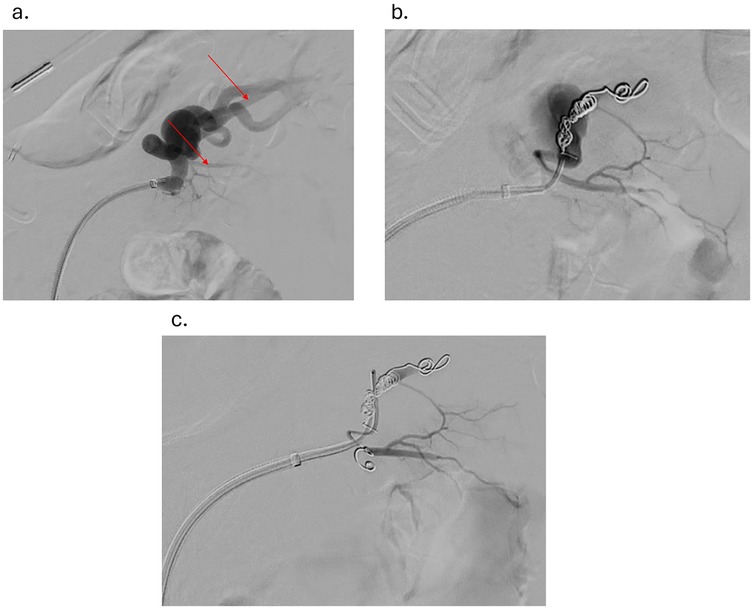

Under sterile conditions, the right femoral artery was accessed using the modified Seldinger technique, and a 5 French vascular sheath was inserted. The splenic artery was selected using a 5-French Cobra catheter and a 0.035-inch hydrophilic Glidewire. A contrast run at the proximal splenic artery showed a large splenic artery aneurysm arising at the bifurcation of major branches. The vascular sheath was exchanged for a larger flexor sheath, which was advanced into the distal splenic artery just proximal to the splenic artery aneurysm. Two minor branches were identified as arising from the aneurysmal sac (Figure 1a). These were individually selected with a microcatheter and embolized with seven Cook Medical® Micronester® embolization coils to prevent backfilling of the aneurysm(Figures 1b,c). Following coil embolization, the remaining dominant branch was selected, and the flexor sheath was advanced across the aneurysm neck, confirming adequate exclusion and distal flow. Then a single balloon-mounted 7 mm Bentley® BeGraft® covered stent was advanced and deployed across the aneurysm neck and unsheathed by slowly retracting the flexor sheath and confirming the appropriate desired location with sequential arteriography (Figures 2a–c). Post-stent deployment angiography showed complete exclusion of the aneurysmal sac with preserved patent flow into the dominant splenic artery branch (Figure 2d). There were no intraoperative and acute postoperative complications. The patient was placed on dual antiplatelet therapy composed of 81 mg aspirin and 75 mg clopidogrel per day. In brief, successful isolation of a large proximal splenic artery aneurysm and preservation of patency of the dominant splenic artery branch were performed by using a covered stent and coiling of minor branches to prevent aneurysm backfilling.

Figure 1. (a) angiogram showing splenic aneurysm with two branches originating from the aneurysm (red arrows) (b) angiogram showing splenic aneurysm after coiling of the first branch originating from the aneurysm (c) angiogram showing splenic aneurysm after coiling of the second branch originating from the aneurysm.